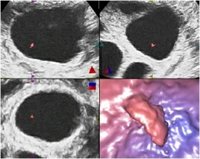

Investigadores de la Universidad Politécnica de Cartagena (UPCT) han desarrollado una nueva técnica que detecta el queratocono, una enfermedad de la córnea que consiste en un adelgazamiento y deformación del tejido corneal.

La nueva técnica de detección del queratocono está basada en un análisis volumétrico de la córnea a partir de unos puntos singulares. Los actuales índices volumétricos presentan dos problemas: por un lado no son muy sensibles a la detección de los casos incipientes del queratocono porque no están definidos localmente en la región primaria de desarrollo de las anomalías estructurales, y por otro lado no registran la descompensación geométrica impulsada por la asimetría presente durante la progresión de la enfermedad.